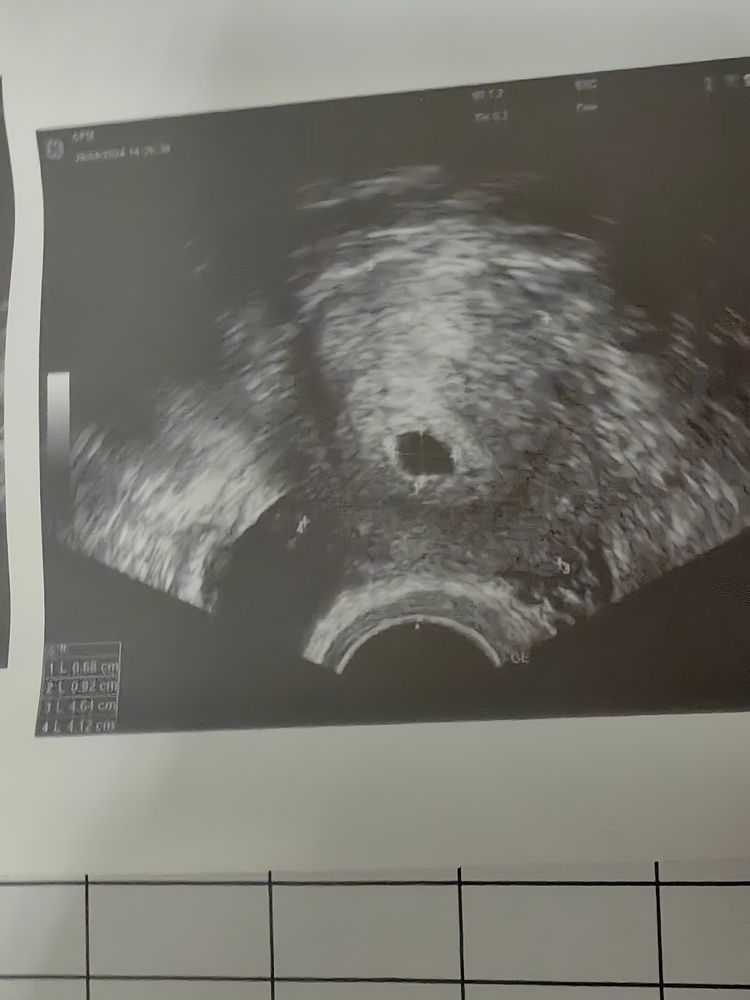

Подсадка была 06.04.2024. Сегодня 20дпп, была на узи, сказали плодное яйцо маленькое, все ли так плохо? Скоро с ума сойду 🥺 я на згт, хгч на 17дпп - 2305, есть ли надежда на успех?

Нормальное пя для срока 7+8,2+8/3 и СВД пя получается 7,7 мм что соответствует сроку 5,3-5,4 акушерских,а 20 дпп с пятидневкой это и есть 5,4 акушерских и жм есть,рано паниковать

Нормальное пя, на 18дпп у меня было 5 мм, вам врач сказала, что оно маленькое?

Aigul Sakaeva, у вас срок 5,3 примерно, все нормально по таблице, ваше пя соответствует значениям хгч, вот у кого выше среднего хгч, у тех оно большое. Посмотрите у меня в дневнике хгч и дпп, примерно как ваши, ничего растем